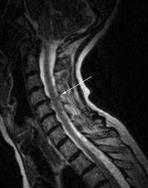

Generalmente es ocasionado por un problema vascular, al mover el cuello, sobretodo de abajo a arriba o en giros bruscos, puede fallar la irrigación de sangre a las zonas del oido encargadas de mantener el equilibrio y ocasionar una sensación de inestabilidad, similar al vértigo, de duración indeterminada. El origen de esta falta de aporte sanguíneo suele ser la contractura de los músculos del cuello, por malas posturas mantenidas, movimientos repetitivos, caídas, degeneración ósea, que altera los puntos de anclaje del músculo al hueso y consecuentemente la alteración de los (propioceptores) sensores de movimiento localizados principalmente en los ligamentos que protegen las vértebras. En estos casos el tratamiento de elección suele ser la práctica de ejercicios de movilidad cervical y en ocasiones la termoterapia superficial que aporta el infrarrojo ayuda a aumentar el flujo de sangre en la zona. Farmacológimante suele tratarse con antiinflamatorios no esteroideos (AINEs) y en algunos casos con relajantes musculares, Siempre según las recomendaciones del médico. Otras afectaciones que pueden ocasionar éste tipo de problemas son las protusiones y hernias discales en la región cervical, que en algún momento pueda provocar la compresión de la médula a este nivel o la irritación del nervio, provocando una sensación vertiginosa o de inestabilidad.